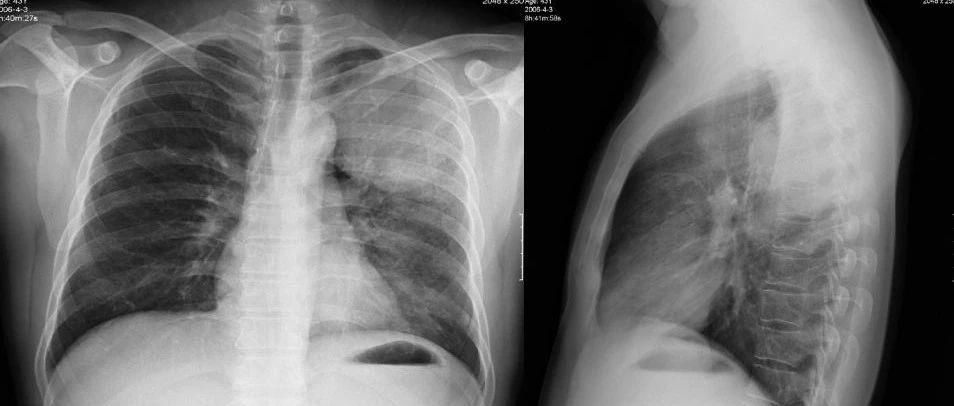

胸膜间皮瘤是一种罕见但极其危险的癌症,主要影响肺部周围的组织。这种疾病通常与石棉接触有关,从接触石棉到发病可能需要20到60年的时间。由于其症状缺乏特异性,胸膜间皮瘤往往在晚期才被诊断出来,此时治疗难度大大增加。

确诊胸膜间皮瘤的唯一方法是进行活检。医生通常会根据患者的具体情况选择合适的活检方法,如通过细针抽取液体或组织样本,或在手术过程中采集样本。一旦确诊,医生还会进行额外的检查,如CT扫描、MRI和PET扫描,以确定癌症的分期和扩散情况。